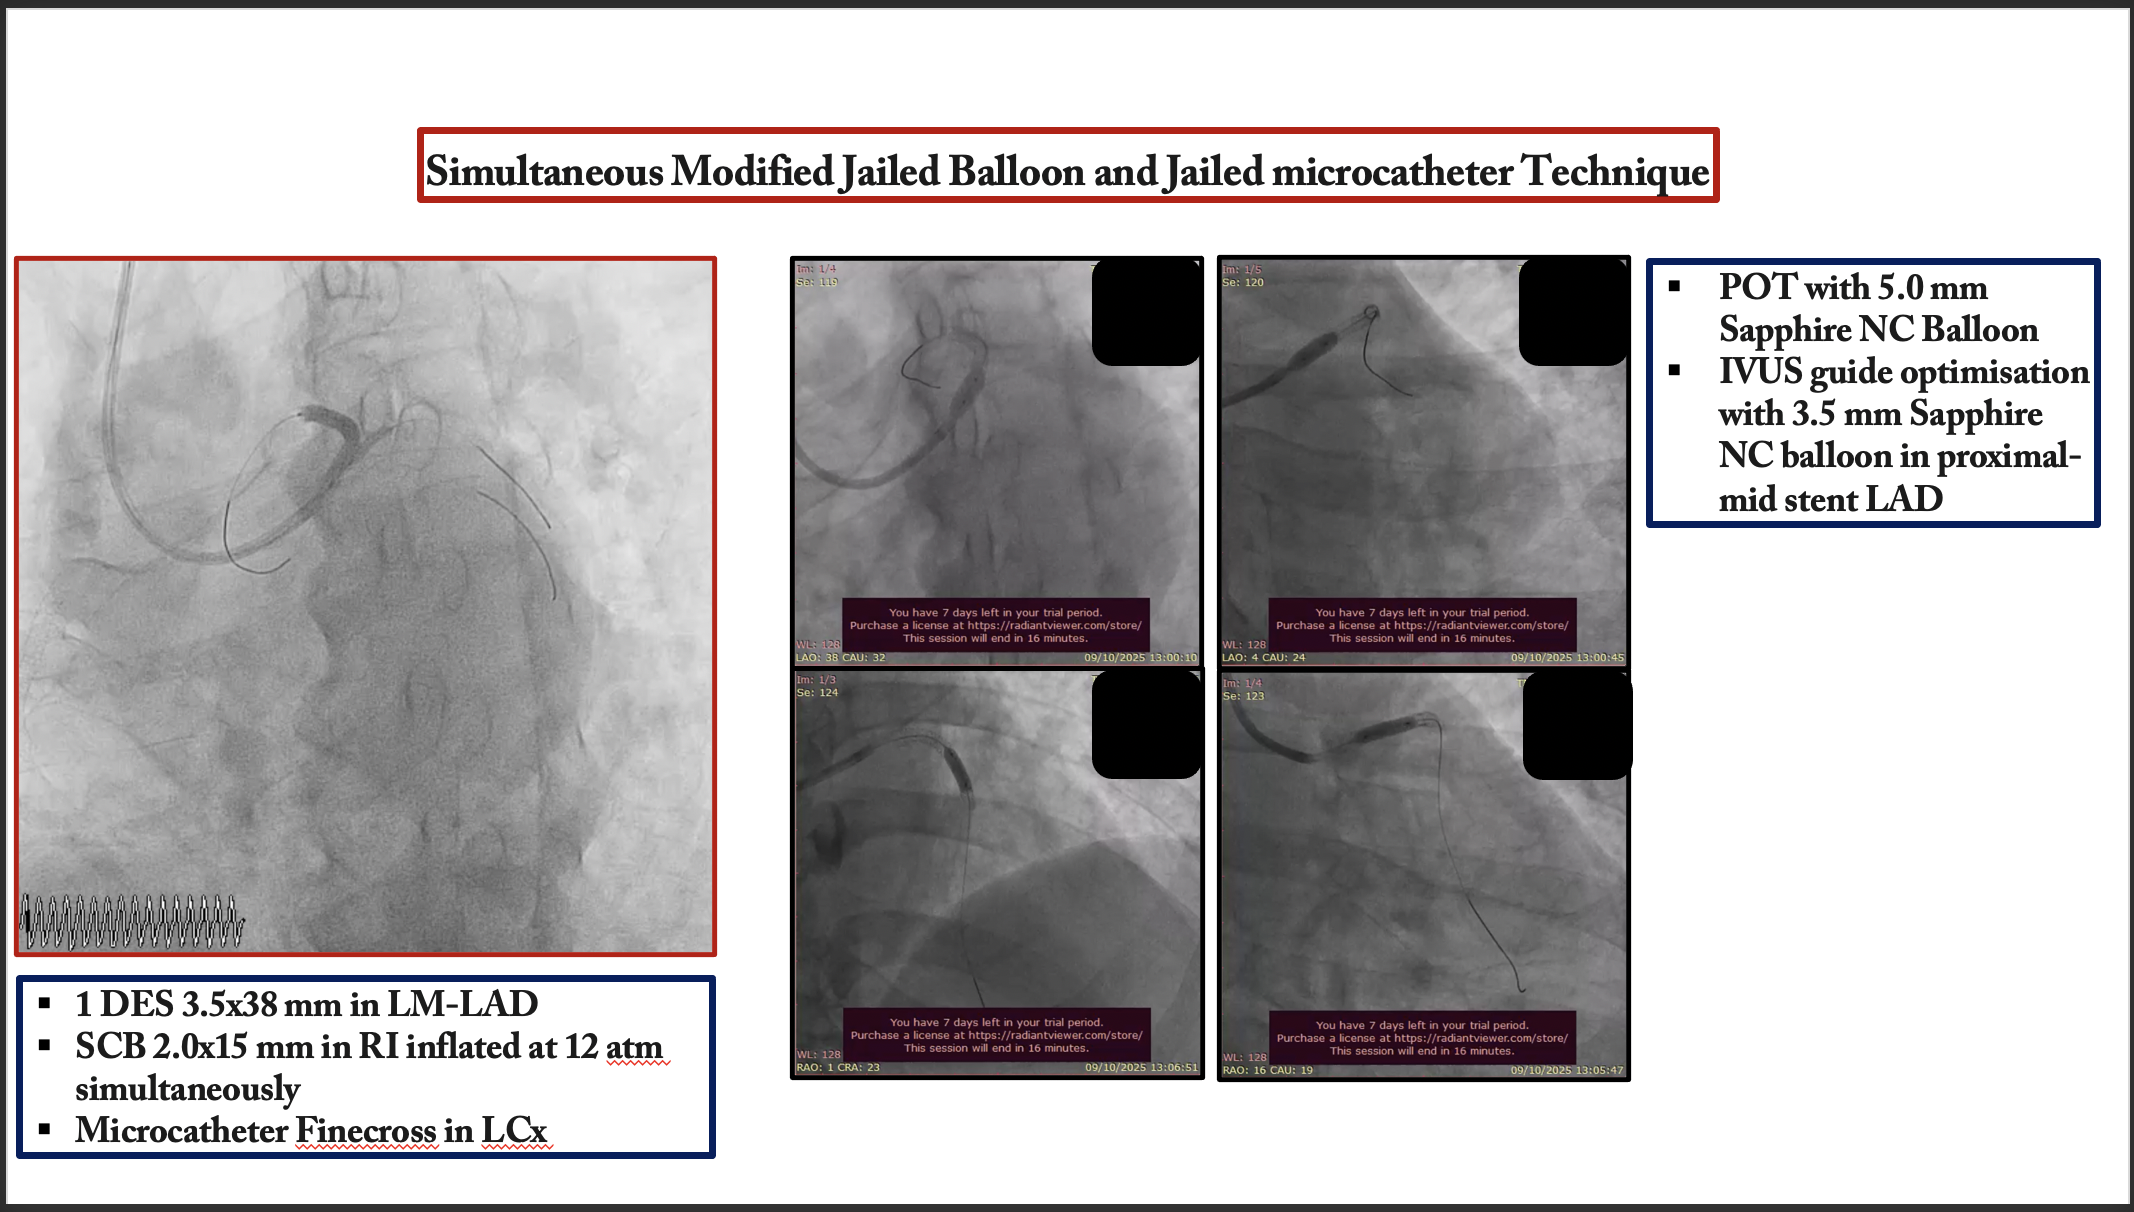

An 7 Fr EBU 3.5 guiding catheter was engaged into the left coronary artery via the right radial artery. A SION guide wire was initially inserted into the LAD. To protect the two large side branches, a BMW guide wire and a runthrough with a Finecross microcatheter were introduced into the intermediate branch and LCX, respectively. According to the angiographic and intravascular ultrasound images, we decided to perform direct crossover stenting from the LMT to LAD using the simultaneous jailed balloon and jailed microcatheter technique. After lesions preparation, Ramus intermediete treated with 1 DEB 2.5x25 mm. A DES 3.5x38 was advanced into the LAD, and a semicompliant balloon 2.0 ¡¿ 15 mm was advanced into the intermediate branch. Subsequently, a Finecross microcatheter was introduced into the LCX. The simultaneous jailed balloon and jailed Finecross technique was then performed. The side branch balloon in the intermediate branch was initially inflated at nominal pressure (12 atm). The main branch stent balloon in the LMT to LAD was then inflated at nominal pressure (11 atm), which simultaneously jailed the side branch semi-inflated balloon in the intermediate branch and the Finecross microcatheter in the LCX. Blood flow was preserved in both the intermediate branch and the LCX after main vessel stenting, and there were no signs of plaque or carina shift into the side branches. Distal LAD was treated with hybrid approach 1 DCB 2.5x35 mm.